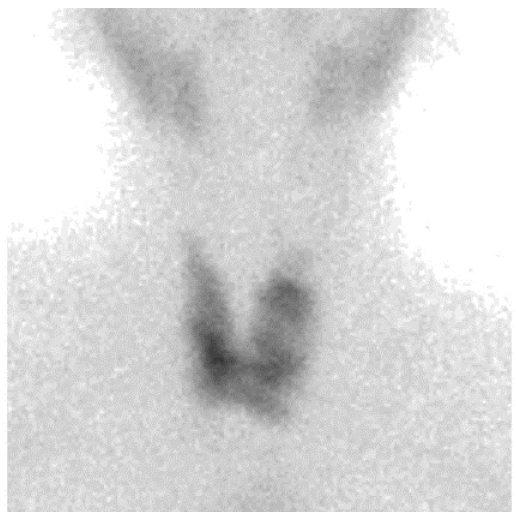

2. Case Report 1

3. Case Report 2